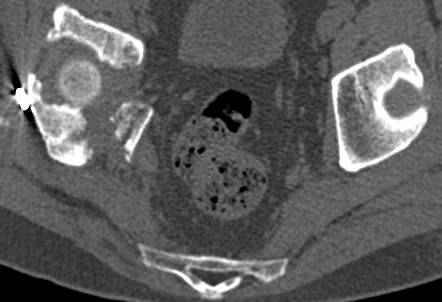

высылаю дополнительно сканы.

Судя по представленным реконструкциям (не очень хорошего качества - много наводок)

мы имеем дело с полупоперечным переломом у которого отломался задний край или его отломали, превратив перелом в полный двухколонный.

По отдельным срезам и тем более по реконструкции трудно судить о сращении крыла и задней колонны с осевым скелетом.

В большинстве случаев при двухколонных переломах

в итоге получается прочный бублик с дыркой. При эндопротезировании в дырку помещается головка, а чашка должна неплохо заклиниться в бублике.

Главное, чтобы бублик не был разорван, что не очень понятно на представленных снимках.

Все выступающие коллеги высказались насчет необходимости стандартных снимков по Judet, потому что для определения тактики лечения переломов вертлужной впадины 3Д снимки малоинформативны.

Из того минимума, что представлено, мне кажется, мы имеем дело с двухколонным переломом вертлужной впадины. Обычно медиальный (центральный) "вывих" головки встречаются в сложных двухколонных переломах со смещением.

Дополнительные сканы